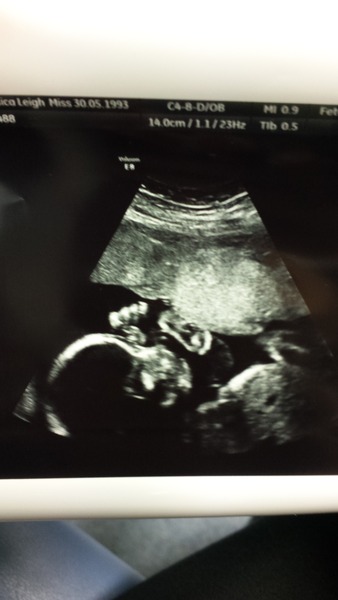

primarynoodle · 22/03/2016 19:36

Just wanted to share my action shot of baby whacking the placenta today during the scan! Everything is looking good so far, biparietal diameter is a bit small but apparently this means pretty much nothing as measurements are so innacurate now!

Cant wait for the next 4 weeks to fly til the next one now! Dont know how you "normal" ladies are coping with no more scans between now and the big day.... id be out of my mind!

Great scan pic primary.

primarynoodle Aww you have a little boxer in there! Mine seems to be doing the same to my bladder.. I've got another scan at 32 weeks cause of a low-lying placenta. At first I was worried, but it's good to know I get another chance for them to check everything is ok.

Great scan primary

Lovely picture of your scan!! Id be going insane if I hadnt booked another 4D scan for just over 6 weeks time! Roll on 7th May so I can see my baby againGrin

Awesome scan pic primary. My little troublemaker had a manic day on Monday, belting me from the middle of the night and almost constant all day. Worried I've got a hyperactive one, but much calmer yesterday, so fingers crossed it was just a result of the vast amount of mini eggs I ate Blush I'll count my blessings that s/he hasn't discovered my bladder yet.

Cute scan pic, primary!